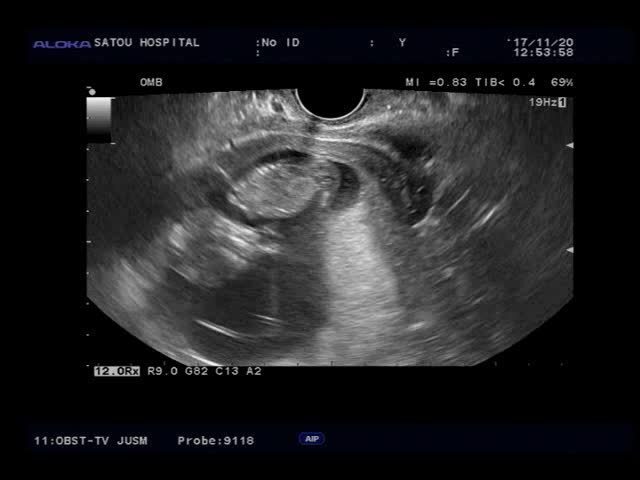

12週1日(12w1d・女の子)|usag1 さん(25歳)

エコー写真撮影時のエピソード:

最初の心拍確認時のエコー。緊急でかかった時だったため、トイレに行っておらず、モヤモヤとしたエコーで、本当に心拍確認できたの?と不安でした。

それから検診の回を重ねるごとにはっきりと人の形になっていくさまが見えて、とてもどきどきで、検診が楽しみだったのを覚えています。